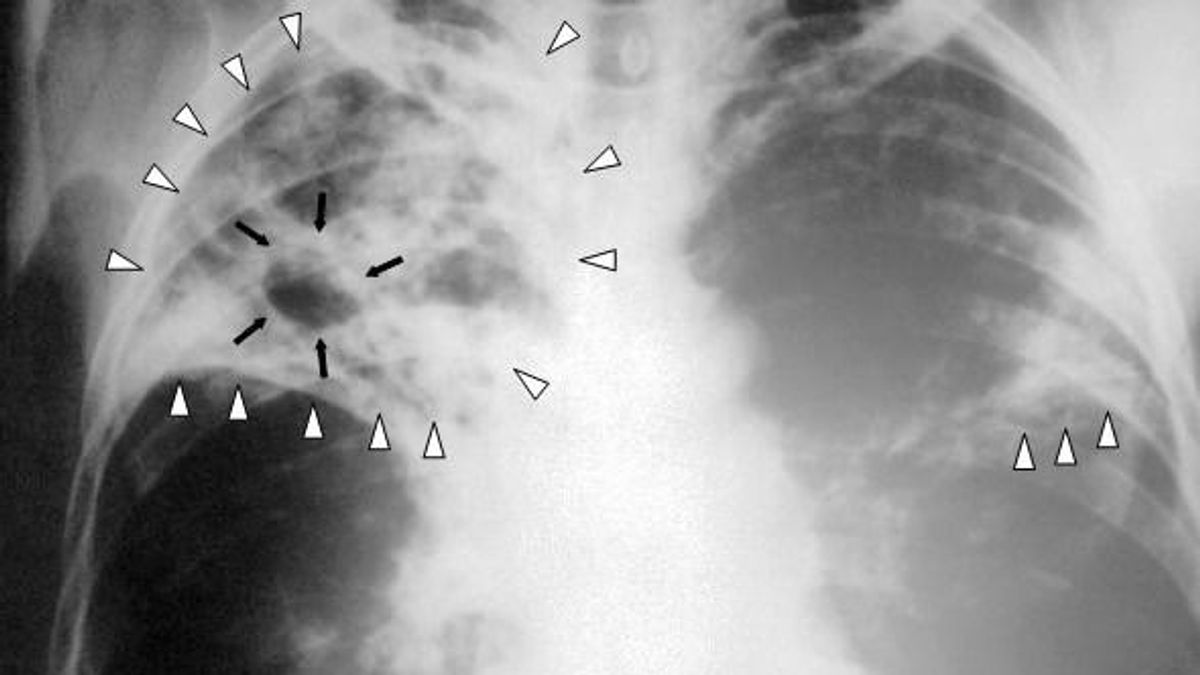

Miért terjed ilyen gyorsan a tuberkulózis az Egyesült Királyságban?

A tuberkulózisos (TBC) megbetegedések száma tavaly 13 százalékkal emelkedett az országban. A betegség bár összefügg a migrációval, mindenkire veszélyes. Egy esetleges lappangó időszak után az idegrendszert támadja meg.

Miért terjed ilyen gyorsan a tuberkulózis az Egyesült Királyságban?

A tuberkulózisos megbetegedések száma tavaly 13 százalékkal emelkedett a szigetországban. A TBC bár összefügg a migrációval, mindenkire veszélyes. Egy esetleges lappangó időszak után az idegrendszert támadja meg.